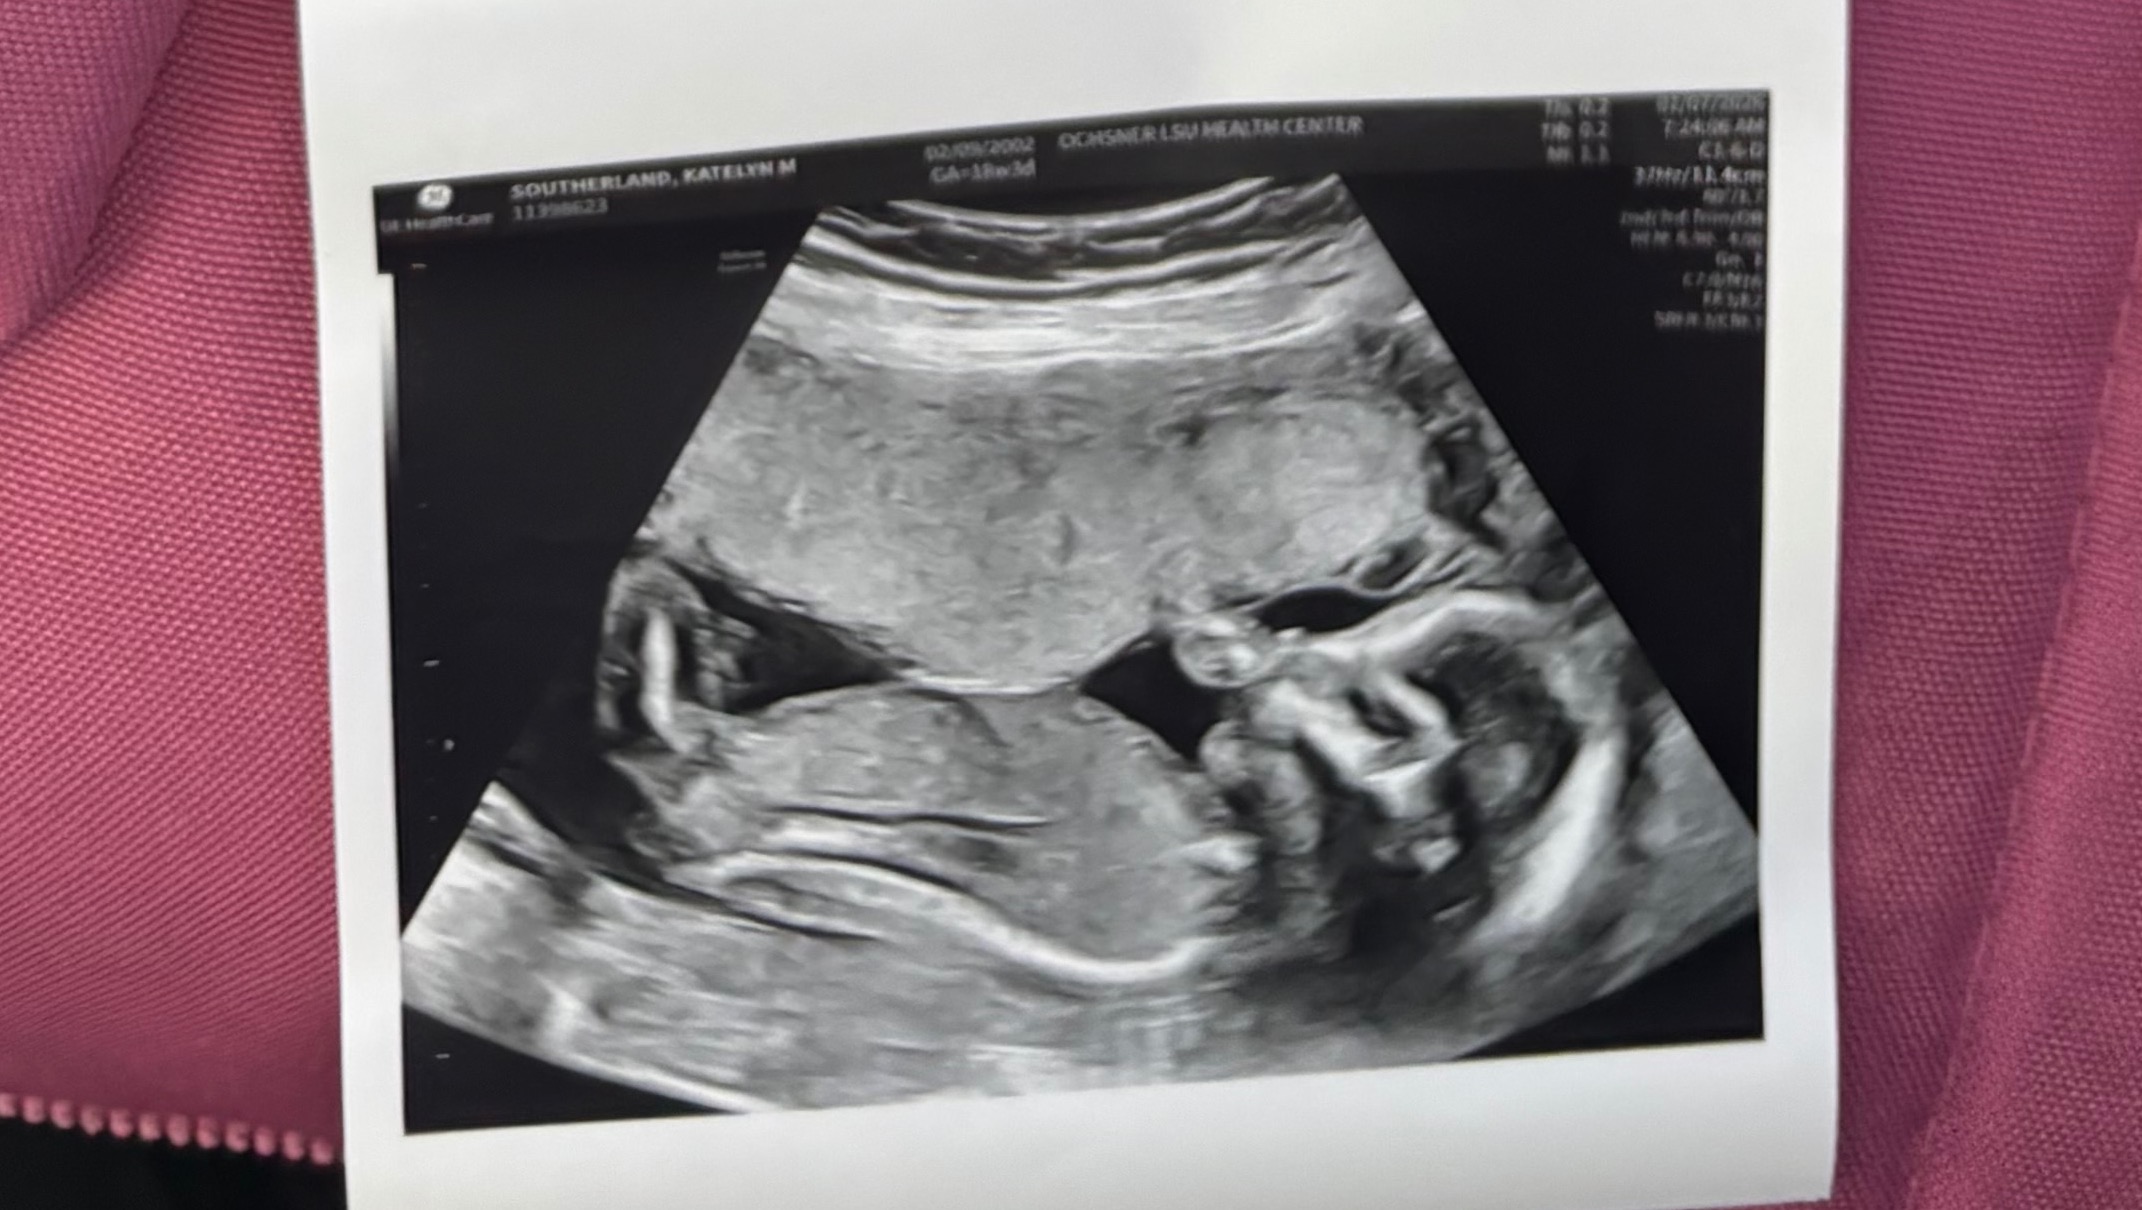

Hi everyone! We have been so excited to announce that we’re expecting a baby boy in May 2026, although I will admit this is not exactly the reveal we hoped for. What I originally expected to be the day I’d be getting ultrasound pictures we could use to announce our son to friends and family, quickly went the opposite direction as we were met with devastating news instead. I apologize in advance for the long reading ahead, but I want to be completely transparent and clarify exactly what is going on for our concerned friends and family!

During my scan, the doctor showed us that baby Christian has Spina-Bifida, as well as clubbed feet and some other birth defects going on. Spina-Bifida means the baby's spinal column doesn't close completely during early pregnancy, leaving the spinal cord and nerves exposed outside of his back. Due to the complexity of our situation, they referred me to Texas Children’s Hospital, which offers a surgery that can be performed during pregnancy to repair and close the opening on his spine. Spina-Bifida Fetoscope Surgery gives babies a better chance at independent walking, better leg function, and significantly reduces the need for brain shunts (hydrocephalus) compared to surgery after birth, by closing the spinal defect in-utero to protect the spinal cord from amniotic fluid damage, improving motor skills, and potentially reducing bladder/bowel issues.